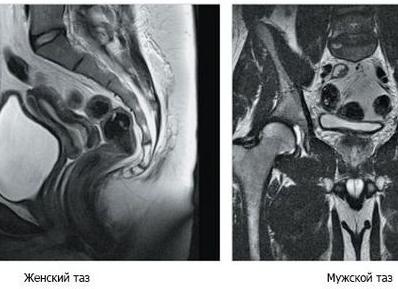

Мрт женских органов малого таза

Магнитно-резонансная томография обладает ярко выраженными преимуществами перед другими методами исследований с визуализацией органов, так как не оказывает влияния с помощью ионизирующего излучения. МРТ органов малого таза у женщин дает возможность адекватно оценить состояние таких анатомических единиц: матки, фаллопиевых труб, яичников, влагалища, мочевыделительного аппарата, ректума, а также кровеносно-лимфатической системы данной области и мягкотканых структур, включая жировую и подкожную клетчатку.Женщинам магнитно-резонансную томографию малого таза проводят с целью выявления следующих патологий: